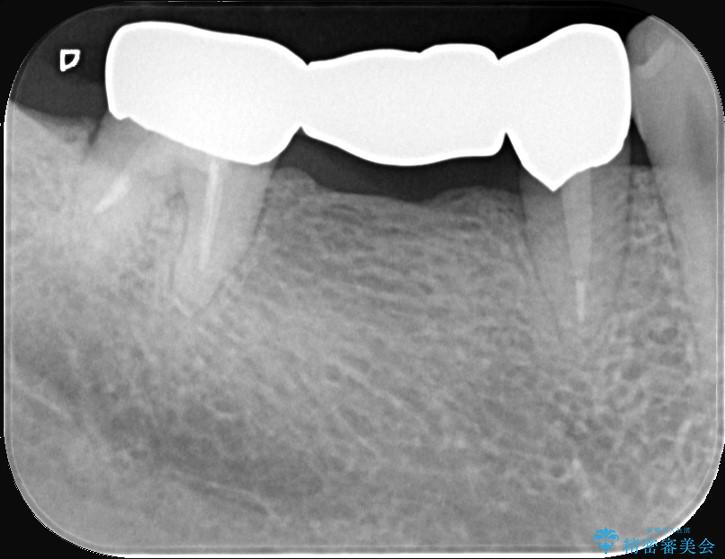

- 主訴:つい先日入れたセラミック(ジルコニア)ブリッジが奥歯部分で割れた。いつも同じ場所で壊れる。これで3度目。

セラミックに比べ、割れづらい金属(ゴールドでのブリッジのやり替えとなりました。

セラミックに比べ、破折リスクの少ない金属を使用したブリッジでのやり替えとなりました。

両支台歯が失活歯のため、どちらかもしくは両方の歯が破折した際、再度ブリッジを除去した治療が必要になるリスクとインプラント治療のご提案もさせていただきましたが、ブリッジでの治療を希望されました。

右下5番は支台歯CR築造を行っています。